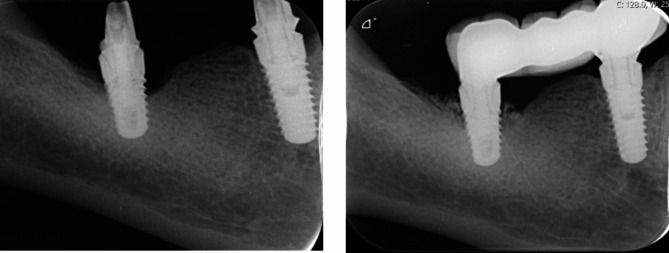

Materials and methods: Nine patients with 11 Class I and III peri-implantitis defects were included. Following implant surface decontamination performed with a chitosan brush, guided bone regeneration (GBR) was performed by means of a bovine derived cancellous bone graft and collagen membrane. Clinical parameters such as full mouth plaque score (FMPS), probing depth (PD), bleeding on probing (BoP), recession, and radiographic bone level (RBL) were recorded at baseline and 1 year following treatment.

Results: All evaluated parameters, including PD, BoP, recession, RBL, and full mouth plaque scores, revealed significant improvements at 1 year follow-up compared to baseline (p < 0.05). The mean PD values reduced from 7.30 ± 1.29 to 3.78 ± 0.65 (p = 0.000). RBL was detected 5.50 ± 1.31 and 1.38 ± 0.74 at baseline and 1-year, respectively (p = 0.010).

Conclusion: Reconstructive surgical treatment of Class I and III peri-implantitis defects with GBR may be an effective treatment protocol when an oscilitating chitosan brush is used for surface decontamination.